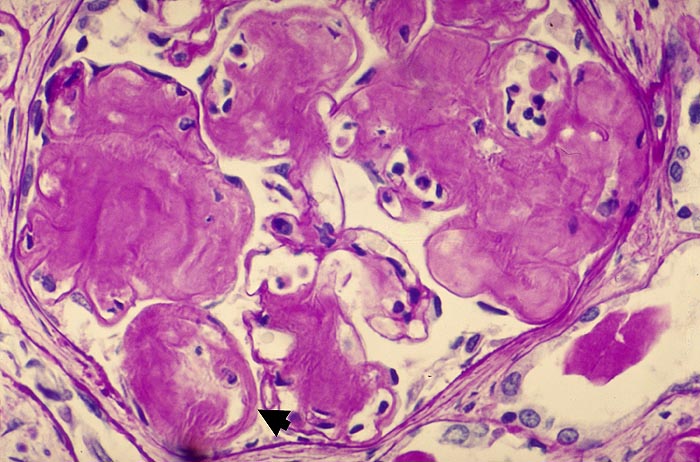

Massive knotige mesangiale Amyloidablagerungen. Die peripheren Schlingen werden teilweise durch Amyloid vollständig aufgefüllt. An anderen Stellen sind die peripheren Basalmembranen massiv verdickt.

Amyloidschrumpfniere 50g. AA-Amyloidose bei chronischer Polyarthritis.

Glomeruläre Amyloidose: anfangs kleine mesangiale, gelegentlich besonders Gefässpolnahe zellfreie Amyloidablagerungen, später teilweise noduläre mesangiale Ablagerungen und Ausdehnung in die Schlingenperipherie mit Durchsetzung der Basalmembran. Schliesslich vollständige Ausfüllung der Schlingenlumina und Verödung der Glomeruli.